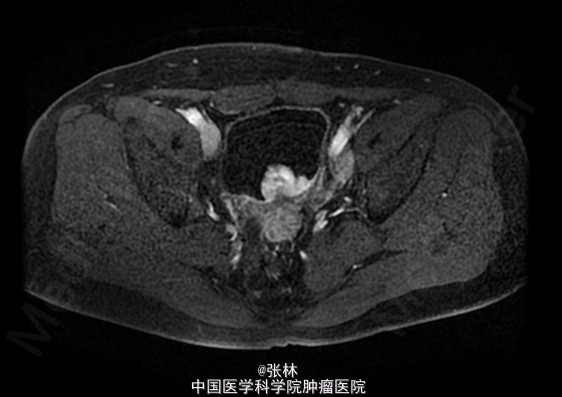

CT:膀胱充盈尚可,内见积气、气液平面;膀胱后壁明显不规则增厚,形成肿物,边界不清,范围约4.8×2.8cm,膀胱壁外缘毛糙,局部与直肠前壁分界不清。考虑:膀胱后壁肿物,与直肠关系密切,考虑为恶性。 MR:膀胱左后壁肿物,与精囊腺及后方直肠分界不清,膀胱充盈状态不同,形态较前改变,现范围约3.6×4.2cm,边界不清楚,T1WI呈低信号,T2/FS呈高信号,DWI扩散受限,增强扫描呈明显不均匀强化,考虑为恶性。